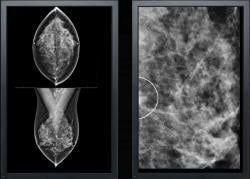

June 11, 2014 — VuCOMP Inc. announced it has received U.S. Food and Drug Administration (FDA) approval for M-Vu CAD for mammography version 3.1. Concurrently, VuCOMP is releasing an update to its CAD (computer-aided detection) station, which includes the ability to process additional standard screening views. Together, the CAD system updates provide radiologists with faster processing time, enhanced workflow and improved parallel architecture.

The M-Vu CAD system uses advanced computer vision algorithms to identify areas of a mammogram that are consistent with breast cancer. M-Vu CAD version 1 was the first product to meet the FDA-recommended reader study standard for proving the effectiveness of mammography CAD. VuCOMP continues to provide systematic product updates, fulfilling the company’s commitment to ongoing enhancements for its customers at no additional cost.

M-Vu CAD is approved for digital mammography systems manufactured by Carestream, Fuji, GE, Giotto, Hologic, Konica Minolta, Philips, Planmed and Siemens. For clinics having a variety of digital mammography systems, M-Vu can now provide a unified solution.

In addition to M-Vu CAD, VuCOMP has developed and commercialized a M-Vu Breast Density solution that received FDA market clearance in December 2013.